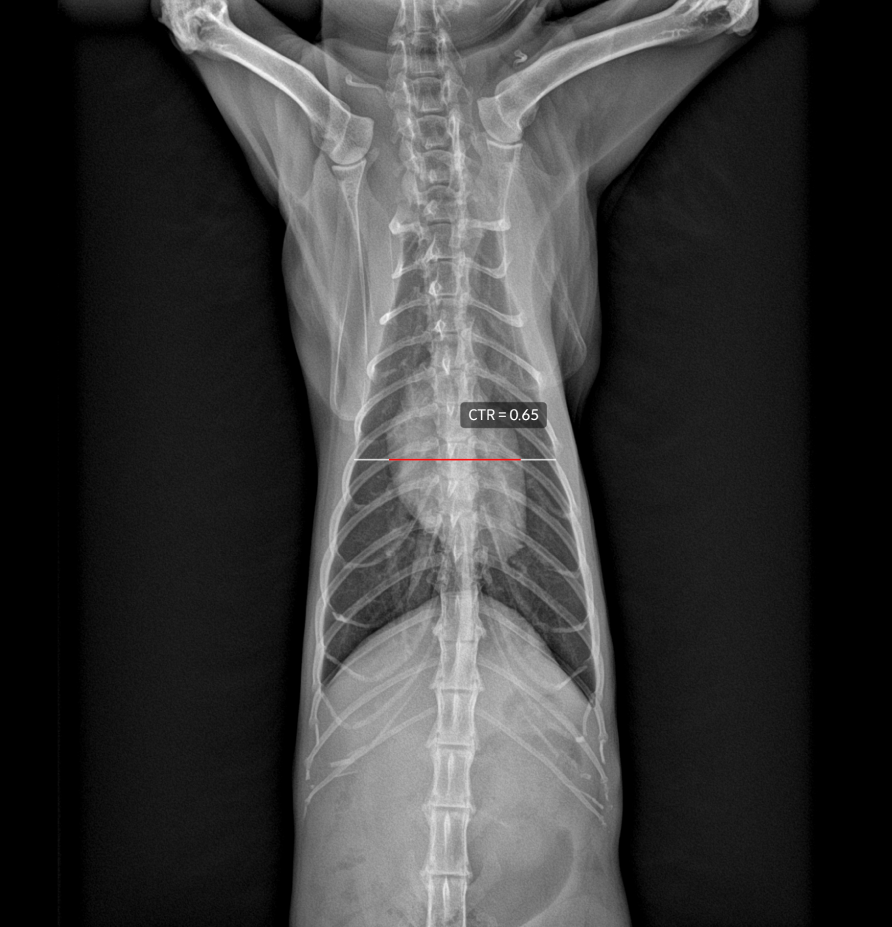

CTR

전반적인 심장 크기를 평가하는 지표로서, VD 흉부방사선 상 심장의 최대 수평 길이를 흉곽의 최대 길이로 비교